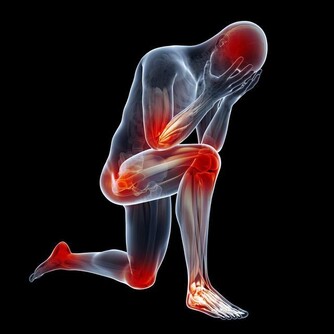

1、全身症狀

疲倦乏力是肝硬化晚期症狀之一,肝硬化晚期症狀多半有皮膚乾枯粗糙,面色灰暗黝黑。

5、出血傾向及貧血

肝硬化晚期常有鼻衄,齒齦出血,皮膚淤斑,胃腸粘膜糜爛出血,鼻腔出血,嘔血與黑糞,女性常有月經過多等症狀。